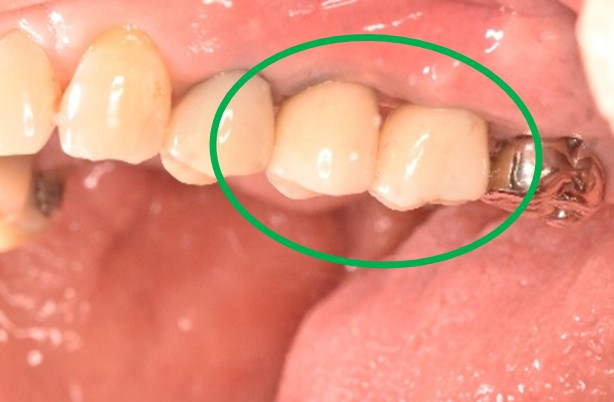

左下の抜けているところに歯を入れたい。

治療内容

インプラントを2本埋入しました。

所感

以前、1本歯がないところを、欠損の両側に被せ物をしてつないだブリッジでした。その2本のうちの前方の歯が歯根の破折を起こし、抜歯になり2本の欠損になりました。この2本の欠損を補う方法には、部分入れ歯、再度ブリッジ、インプラントの3つの方法があります。部分入れ歯もブリッジも欠損部分の負担をほかの歯に負わせるため、支台になった歯は負担が大きくなり、虫歯、歯周病、歯根破折の危険性が高まり、さらに歯を失うことになります。インプラントは、それ自身が単体で植立しているため他の歯に負担を負わすことがありませんので、咬合を回復させるだけではなく、他の歯を守る役割もあります。今回もX-Guideを使った埋入で、安心安全に行うことできました。

インプラント2本:¥363,000×2本=¥726,000(税込)

Before

After